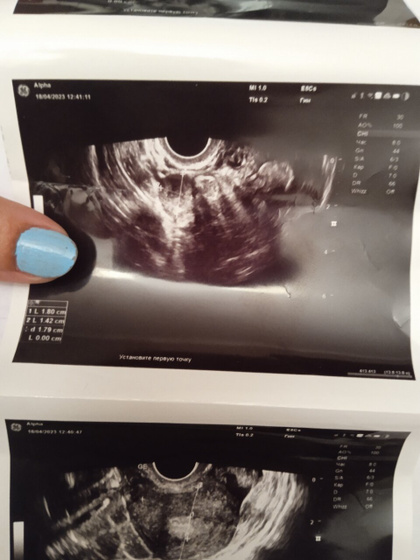

Девушки здравствуйте скажите пожалуйста что это такое задержка 18-19 дней. муж с сво на две недели приехал, последние месячные были 10 марта. Поехала на УЗИ сдала хгч в альфе но внятного ни чего не сказали единственное сказали жёлтое пятно и все. Я просто не понимаю. Объясните пожалуйста